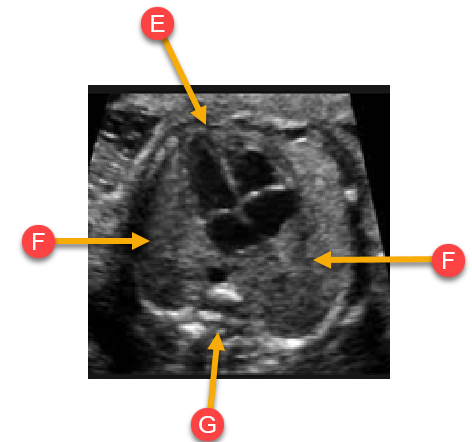

Label the anatomy with the arrows

E. Heart (apex)

F. Lungs

G. Spine